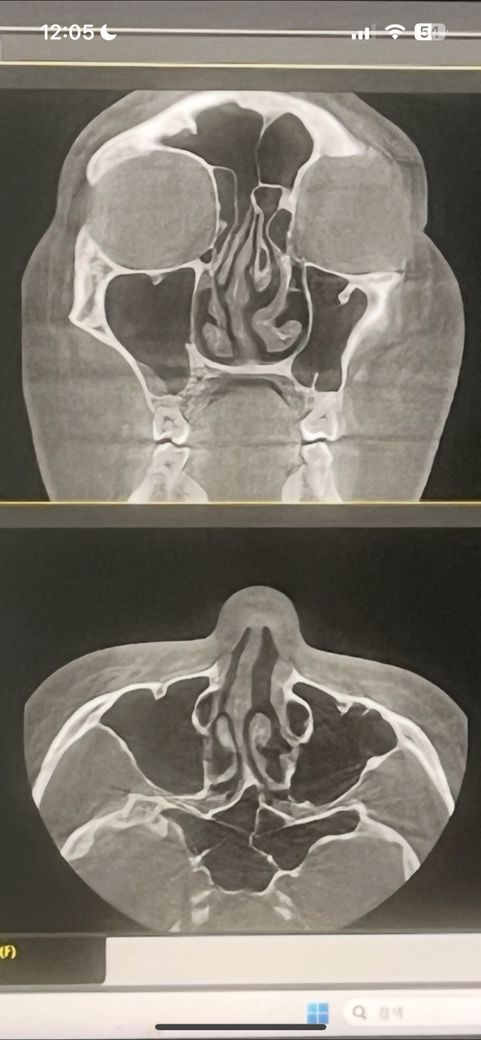

물렁뼈 안경쓰고 주먹으로 맞았는데 ….

몇개월됬어요 맞은지는…. 맞고 6일후에 갔는데 물렁뼈가 살짝 휘었데요.. 6일지나니까 갑자기 코가 굳어가는것과함께 뼈가 엄청쪼이는기분과 함께 뼈가 산산조각이 나는것같아 으스러지는기분을 받으면서뼈가 찌릿거리면서 아! 걸이고 잘때 숨이 안서지고 누워있으면 뼈가 쪼이면서 뼈가 순환이 안되어서..뼈와뼈가 마찰이되는 이상한기분이 들어서 잠잘때도 힘이 들었어요… 뼈가 휘어서ㅠ그런거겠죠? 맞고 6일 뒤에 가니까.. 그뒤로 계속 그러더라고요.. 코가 놀랬던같다면서 약을 지어드릴까요했는데 저는 그냥 거부했었어요.. 약먹으나 안먹으나 상관없었겠죠? 약을 먹는다고 뼈가 데돌아오는거였을까요? 치료방법은 없다네요. 이비인후과에서..

• 1번 째 사진

물렁뼈가 휘었다는 진단을 받은 후, 코가 굳어가고 뼈가 쪼이는 기분, 찌릿거리며 아픈 증상은 물렁뼈에 충격이 가해져서 발생할 수 있는 불편함입니다. 물렁뼈는 연골로 이루어져 있기 때문에 외부 충격으로 인해 일시적으로 형태가 변하거나 염증이 생길 수 있어요. 약을 복용한다고 해서 물렁뼈가 돌아오는 것은 아니지만, 염증을 줄이고 증상을 완화할 수는 있습니다.

만약 증상이 계속해서 심해지거나 숨쉬기가 어려울 정도로 불편하다면, 추가적인 검사나 다른 전문의의 진료를 받는 것이 좋습니다. 치료 방법이 없다고 들었더라도, 다른 진료를 받아보면 더 나은 해결책을 찾을 수 있을 수 있습니다